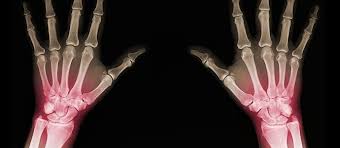

في مقالنا بعنوان "ما هو التئام العظام بشكل خاطئ وعدم التئامها؟ ما هي أعراضهما؟ وكيف يُعالجان؟"،...